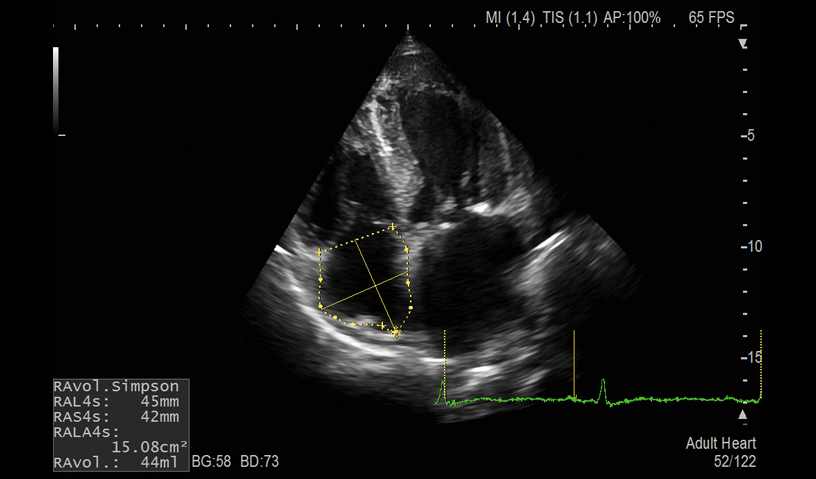

RA Volume

- Auto LV, LA and RA Volume and FAC